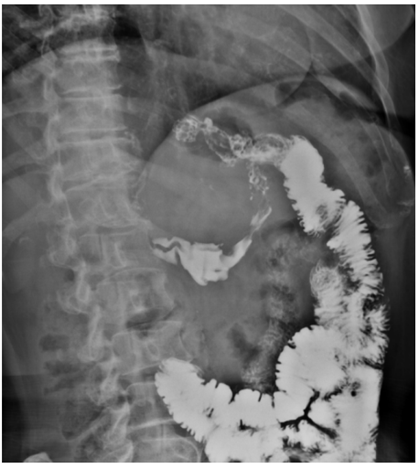

Mulher de 55 anos, submetida à cirurgia bariátrica há 6 meses sob técnica de bypass gástrico em Y de Roux, queixa-se de desconforto epigástrico e de dores intermitentes no abdome superior há 3 meses, sendo solicitado pelo médico cirurgião exame contrastado do esôfago-estômago-duodeno, representado pelas duas imagens abaixo. Obs.: contraste administrado por via oral.

I. Há refluxo de contraste da via alimentar para a via biliopancreática por incompetência da anastomose terminolateral jejuno-jejunal.

II. Os achados evidenciam a presença de fístula entre a anastomose bolsa gástrica-alça jejunal e o estômago excluído.

III. Observa-se extravasamento de meio de contraste para a cavidade abdominal, achado suspeito para deiscência da anastomose bolsa gástrica-alça jejunal.